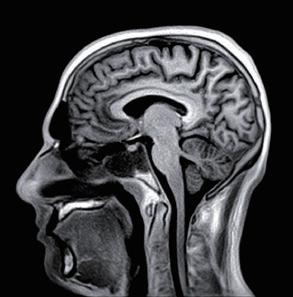

Fig 1: Next generation MRI is being used to gather data on brain tissue volumes Dr. Steve McNally

From this season at Manchester United Football Club, we have started to gather data by using MRI (see fig 1) to measure volumes of brain tissue in specific areas, to monitor for a decrease in volumes over time. If the volumes become unusual or deviate from the norms that we would expect, it may help us identify early changes of CTE that need closer monitoring. This is a new, long-term data gathering study in our cohort of players that has been facilitated with the new next generation MRI3 now in place at our medical centre.

MRI is also an excellent choice of tool for the diagnosing and monitoring of Chronic Traumatic Encephalopathy (CTE), the result of repetitive brain trauma from blows to the head and repeated episodes of concussion, which in football may have come from player contact or heading the ball. It is a hot topic in all contact sports such as boxing, rugby and martial arts and follows research at the University of California, Los Angeles (UCLA) using MRI as the option to explore CTE without any dose implications to patients2

32 // VISIONS SPECIAL